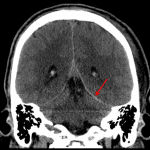

- Thin acute subdural hematomas layering along the left cerebral convexity, interhemispheric falx, and left cerebellar tentorium

Thin acute subdural hematomas layering along the left cerebral convexity, interhemispheric falx, and left cerebellar tentorium, measuring up to x mm in thickness.